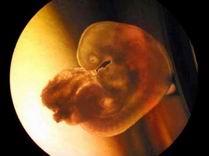

Human Embryo Nurtured Outside Mother's Body

A human embryo born in a fostering liquid is shown under a microscope to the public in Northeast China's Liaoning Province, April 15,2004. It's the first time in China that an embryo is successfully nurtured outside a mother's body.

Doctor Wang Tong of the province's Research Institute of Family Planning Science invented the new method, which can enable a mother diagnosed with certain illness to produce a baby with her egg outside her body and save her from risks. So far, Wang and his team have nurtured 28 such embryos.